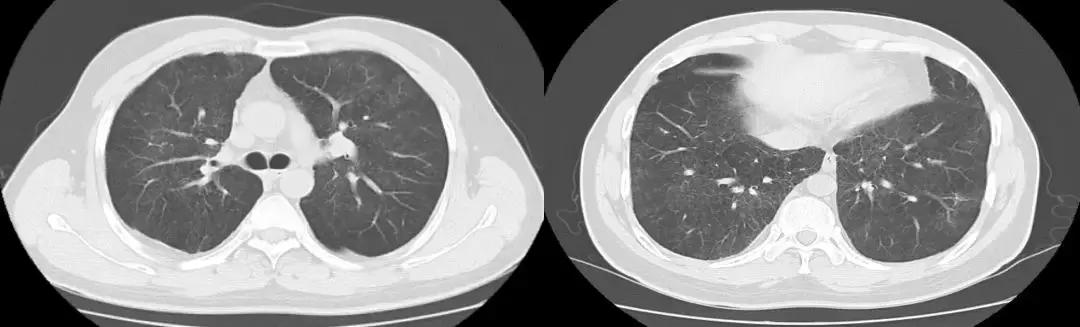

胸部CT(2017-7-31 我院门诊):两肺野弥漫磨玻璃影,性质待定;两肺上叶陈旧性病变。(如下图)

胸部CT(2018-1-18 我院门诊):两肺野弥漫磨玻璃影,较前变化不明显;新增左肺下叶基底段片状密度增高影,建议治疗后复查;两肺上叶陈旧性病变: